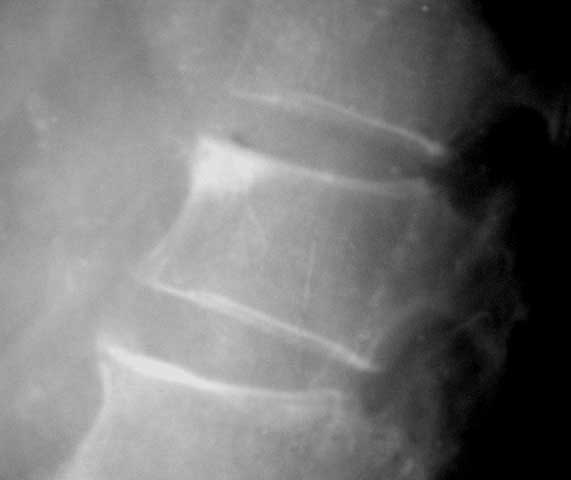

f/43y,腰部痛。

典型椎体致密性骨炎.(l1)

致密性骨炎是一种骨质硬化性疾病.多见于髂骨 腰椎 骶骨和耻骨.

至今病因不详,也就不必再议.  腰椎好发于l前上角,呈三角形影.

椎间隙正常.

l1椎体前上部致密影,为典型的致密性骨炎。此外,该例尚有腰椎骨质增生改变。

腰椎致密性骨炎

图片来源徐爱德主编,骨关节疾病影像学图鉴p197

腰椎好发于l前上角,呈三角形影.